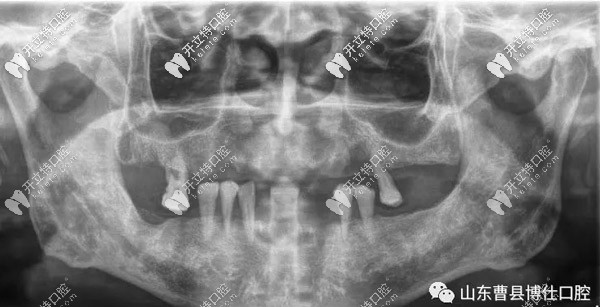

口腔上下只剩7顆牙,對飲食帶來了很多不便,經(jīng)檢查發(fā)現(xiàn)徐大爺因患牙周病導(dǎo)致牙齒松動、牙齦萎縮、牙槽骨吸收。

經(jīng)過一個半小時的手術(shù)時間,徐大爺上頜和下頜各植入8顆種植體,縫合傷口后,拍片顯示植入位置非常好。